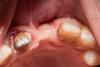

SashaDoc Опубликовано 15 октября, 2013 Поделиться Опубликовано 15 октября, 2013 (изменено) Сделал на днях. Вестибулярный дефект в обл 2.1.Сорри за качество, подходящего объектива/пыхи пока нет. Критика очень приветствуется Изменено 15 октября, 2013 пользователем SashaDoc 2 Ссылка на комментарий

rivezico Опубликовано 27 октября, 2013 Поделиться Опубликовано 27 октября, 2013 Сделал на днях. Вестибулярный дефект в обл 2.1.Сорри за качество, подходящего объектива/пыхи пока нет. Критика очень приветствуется верхние 3 винта - тенты? Ссылка на комментарий